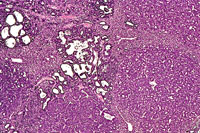

Multiple biliary and hepatocellular hyperplastic and neoplastic lesions in the liver of a 4-week-old transgenic mouse.

Confluent biliary and hepatocellular neoplasms totally occupying the left liver lobe of a 4-week-old transgenic mouse.